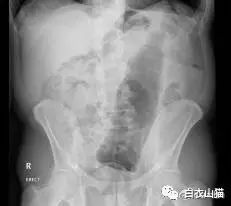

医生给他检查的时候,发现已经有腹膜炎症状,怀疑肠梗阻,拍了个片子,就是上面那个片子:一条大黄鳝在肚子里。

上面是前几年一名患者大肠里的黄鳝。